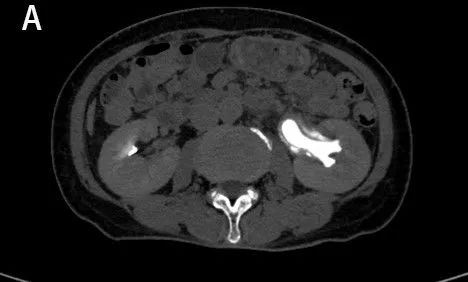

图1A

图1B

图1A、B:CT平扫示左肾及左侧输尿管扩张积水。